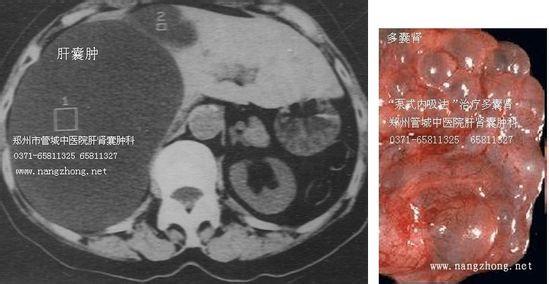

多囊肝多囊肾,其实就是多囊肝以及多囊肾的“结合体”。那患上多囊肝多囊肾应该如何治疗呢?下面我们就一起来看一下。

多囊肝的症状

1、患上多发性肝囊肿后,首先表现出来的是消化道症状。如消化不良、食欲减退、恶心、呕吐和右上腹痛,但程度不重。肝脏肿大和右上腹肿块,触之呈囊性感,无明显压痛。继发感染后可出现寒战和发热。

2、多发性肝囊肿的肝表面可触及散在的囊性结节。如囊内出血,合并感染或带蒂囊肿扭转时,可有急腹症表现。少见有巨大囊肿压迫胆总管或肝管出现黄疸的情况,可无阳性体征,部分患者可触及腹部包块。